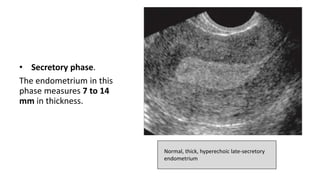

• Secretory phase.

The endometrium in this

phase measures 7 to 14

mm in thickness.

Normal, thick, hyperechoic late-secretory

endometrium